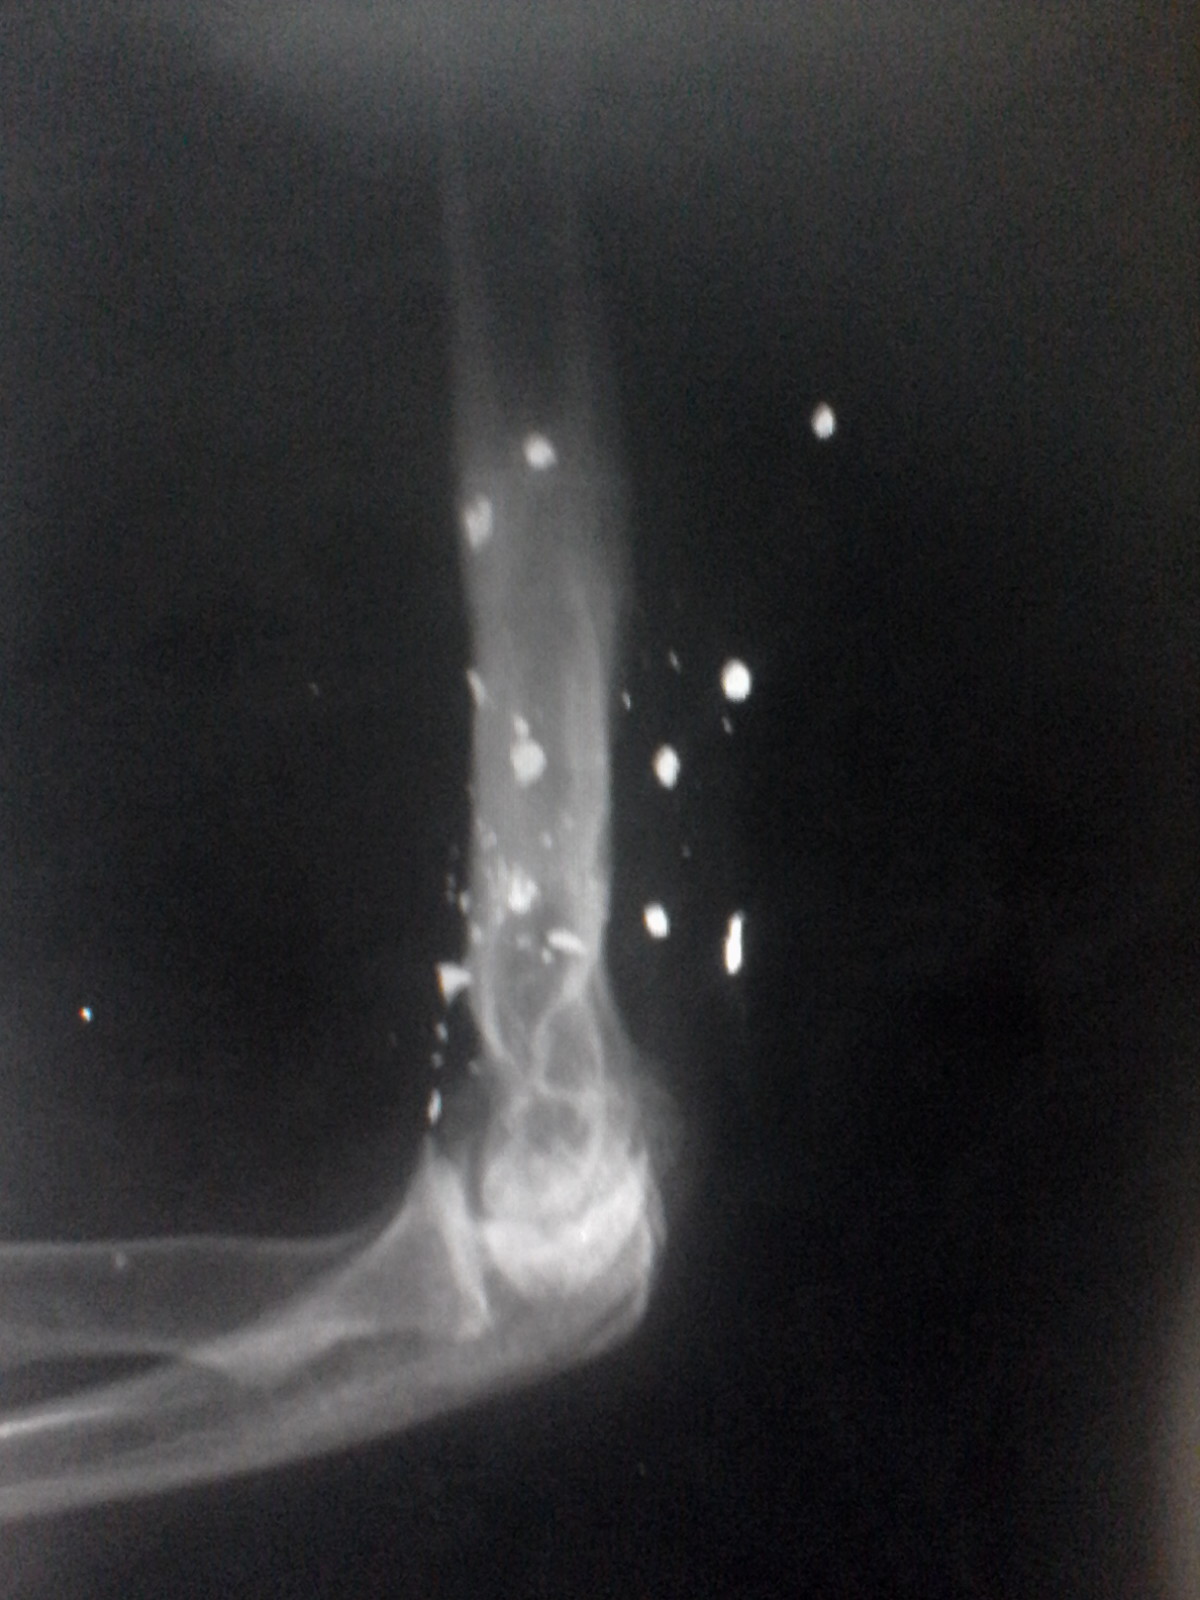

Diagnostico medico por Imagen